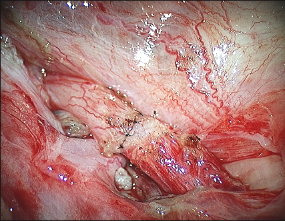

Once the inner luminal sutures are tied, the knots are cut precisely. Because of the very small size of the vas deferens lumen, any redundant suture material can obstruct the flow of sperm along the vas deferens. Likewise, sperm leakage outside of the lumen can cause obstruction of the vas deferens. A water tight closure of the vas deferens mucosa prevents sperm from leaking out of the vas deferens after the procedure.

The outer serosal sutures are equally important in the reverse vasectomy procedure. These sutures relieve tension off of the finer inner luminal sutures and prevent the ends of the vas deferens from separating after the reverse vasectomy procedure. Liberal placement of these outer serosal micro-sutures needs to be done under a microscope as well to ensure that the ends of the vas deferens are precisely approximated.